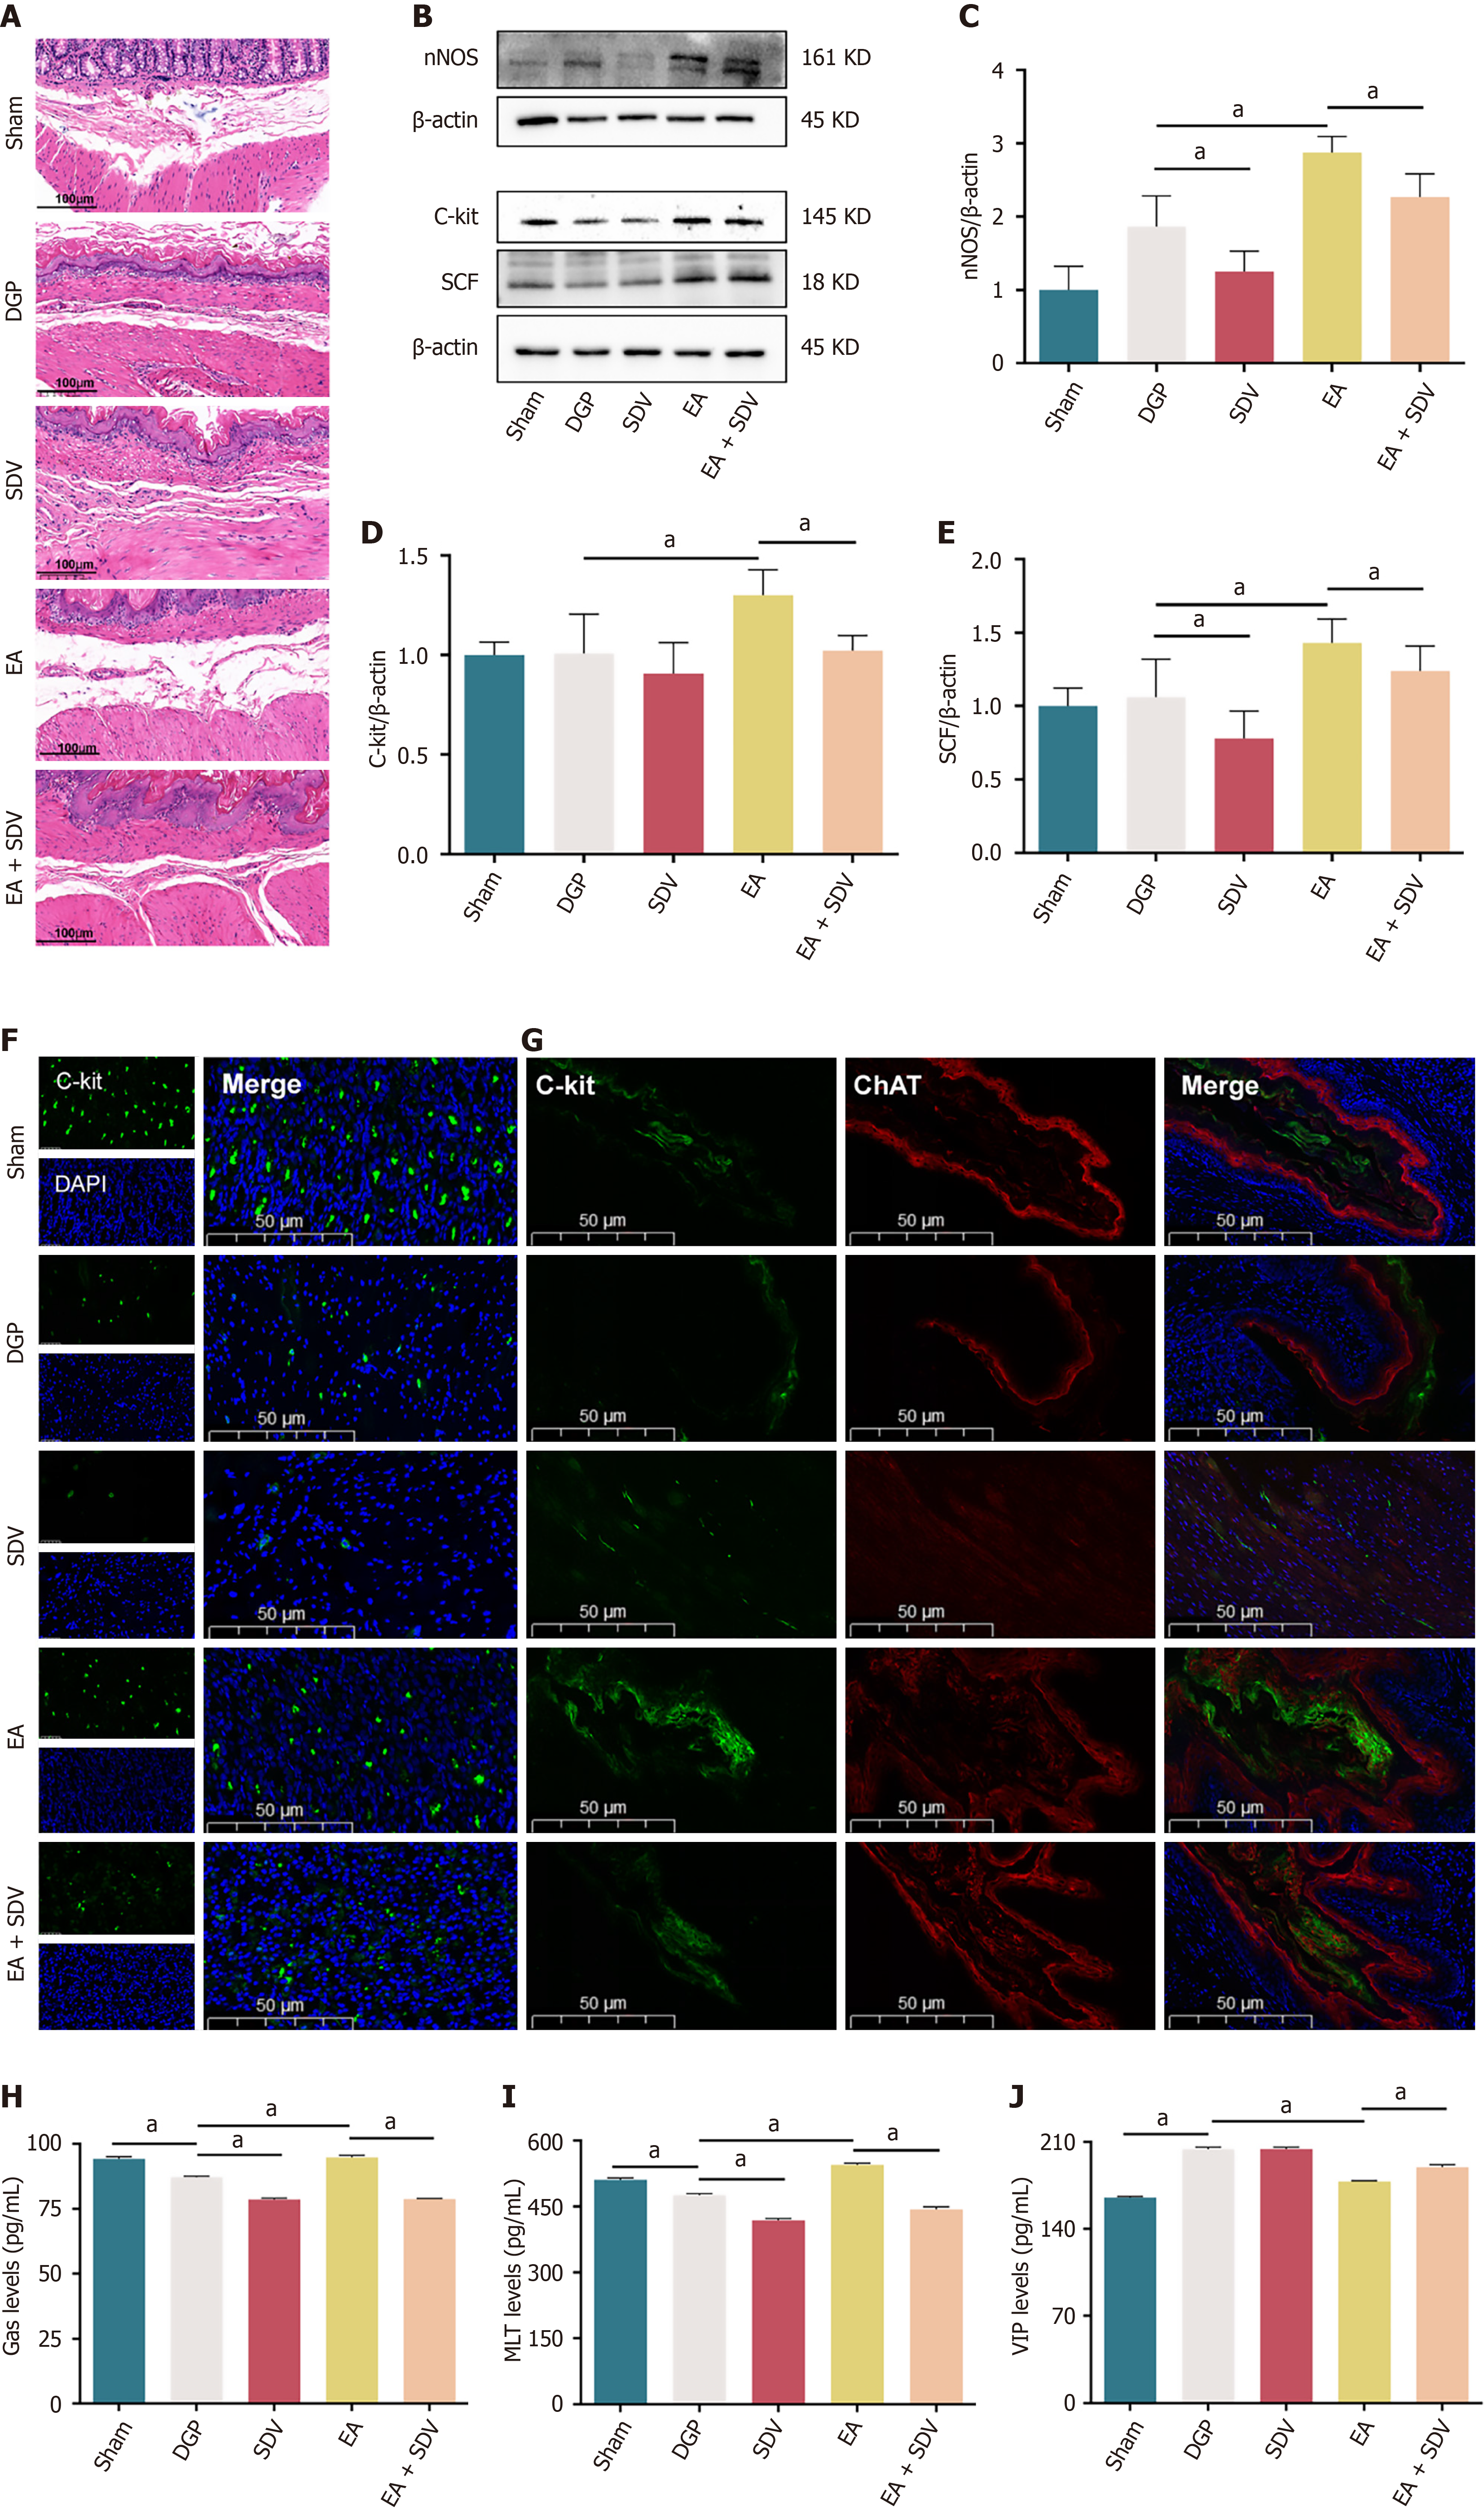

Histological analysis via HE staining revealed that EA ameliorated gastric pathology in DGP rats, characterized by reduced inflammatory infiltration and restored smooth muscle alignment. Conversely, SDV appeared to counteract these benefits, sustaining submucosal collagen deposition and mild smooth muscle disorganization (Figure 8A). In addition, the results of the western blotting analysis demonstrated that EA significantly increased the expression of nNOS, C-Kit, and SCF, while SDV significantly reduced the expression of these proteins in comparison with rats treated with EA (P < 0.05; Figure 8B-E). Immunofluorescence corroborated these findings: EA enhanced C-Kit expression, which was suppressed by SDV (P < 0.05; Figure 8F). Furthermore, the co-localization of C-Kit and ChAT further confirmed EA’s activation of vagal-ICC interactions, an effect that was attenuated by SDV (P < 0.05; Figure 8G). Furthermore, gastrointestinal peptide profiling revealed that EA-mediated upregulation of Gas and MLT was accompanied by suppression of VIP, with SDV reversing these trends (P < 0.05; Figure 8H-J). Collectively, these results establish that EA improves gastric dysmotility by activating subdiaphragmatic vagal efferent pathways, which regulate smooth muscle integrity, ICC function, and neuropeptide balance in DGP.